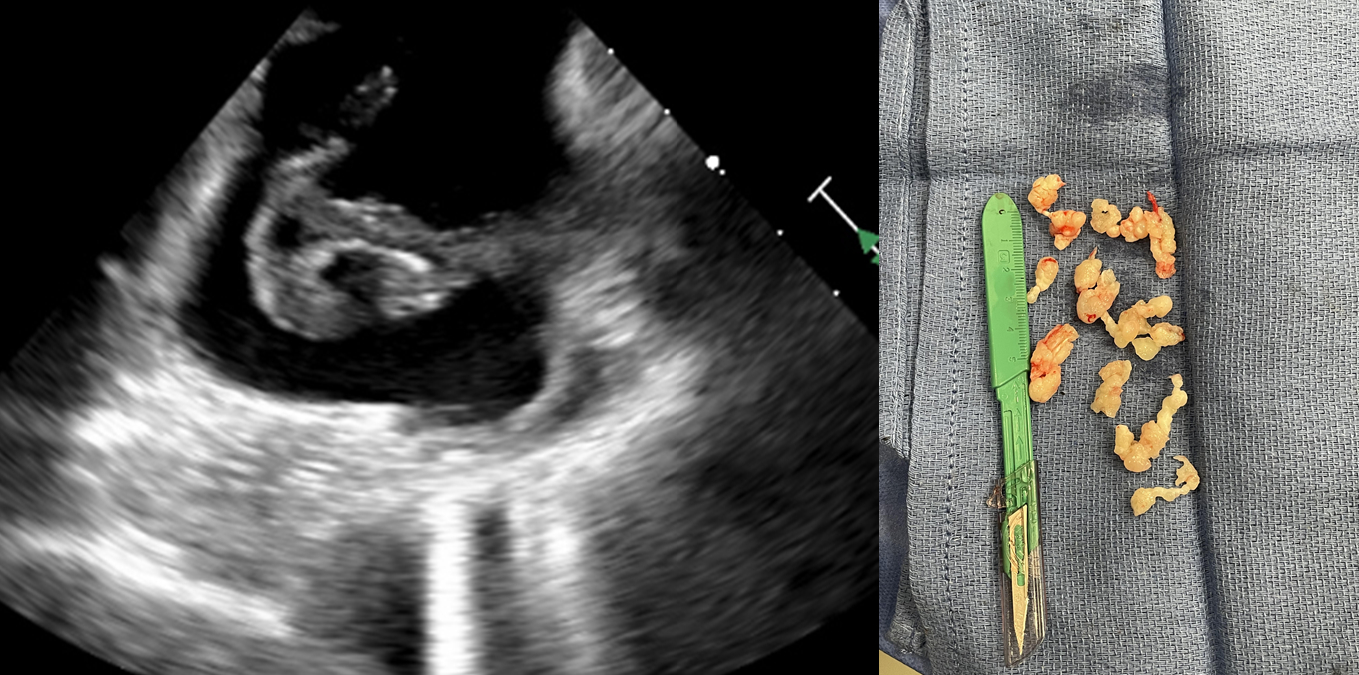

Case Presentation: 59F with a past medical history of SCLC status-post chemotherapy and radiation presented for evaluation of worsening left upper extremity pain, paresthesia, motor weakness, and neck pain. During the hospital admission, an echocardiogram demonstrated extensive thrombus from the Superior Vena Cava (SVC) into the right atrium (RA) and an irregular echogenic 37 mm x 26 mm mass partially attached to the posterior leaflet of the tricuspid valve. The RA mass was successfully removed by mechanical thrombectomy. Pathological results of the RA mass revealed significant malignant epithelioid and spindled neoplasm with myxoid stroma– concerning for myoepithelial disease.